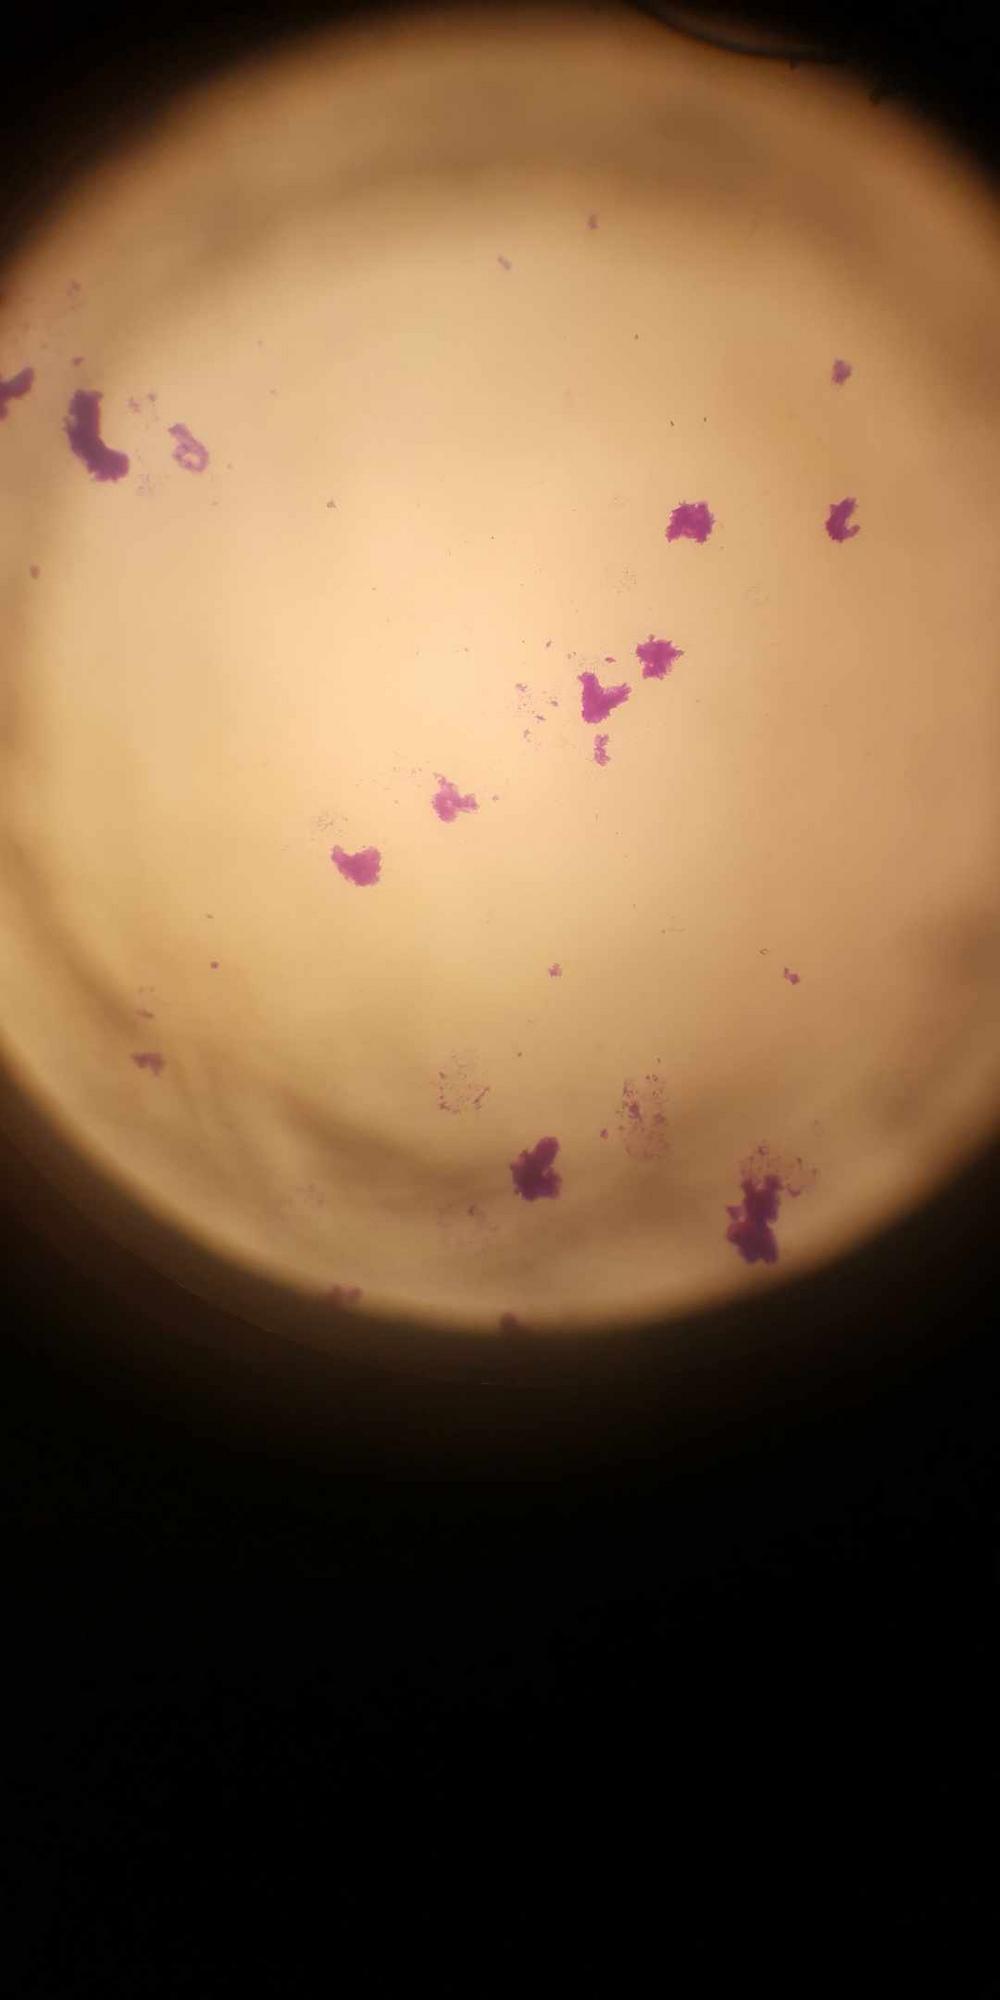

• 18.8.2 观察吞噬细胞的吞噬作用

• 18.8.3 直接凝集反应结果

• 18.8.4 免疫器官、免疫注射结果及分析